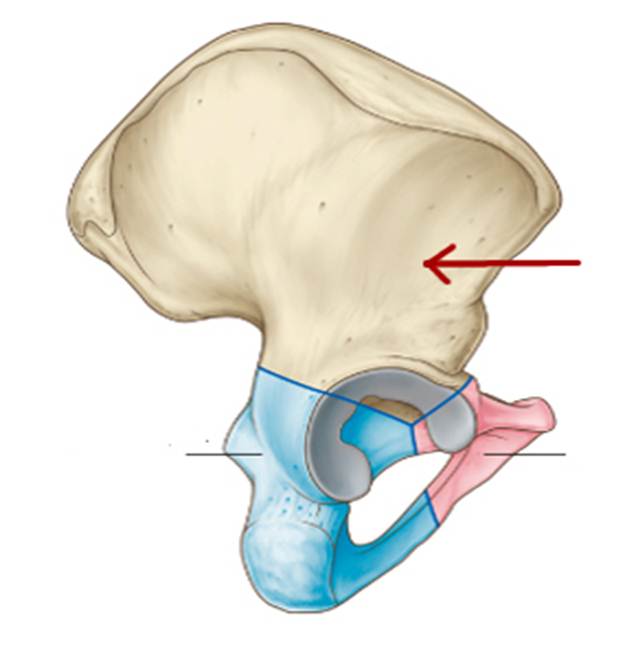

S: На рисунке обозначен art. Coxae (латинский язык).

S: Стрелки указывают на lig. iliofemorale

S: Стрелка указывает на lig. pubofemorale

S: Стрелка указывает на labrum acetabuli

S: Стрелка указывает на lig. Capitis femoris

S: Стрелка указывает на facies lunata